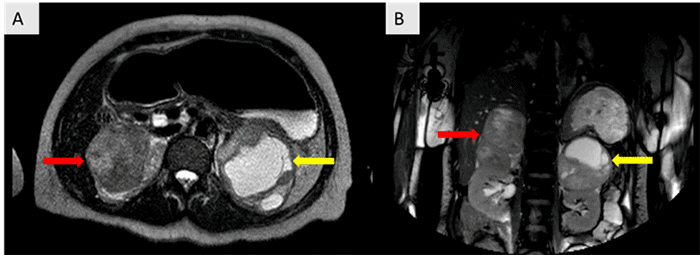

An abdominal and pelvic CT scan was performed, which demonstrated enlarged bilateral adrenal glands (right: 7.0 × 6.9 × 10.8 cm, left: 9.4 × 9.5 × 8.7 cm) with internal heterogeneous hypodensities, concerning for bilateral adrenal hemorrhage, and a markedly dilated rectum measuring up to 10.1 cm in transverse diameter (Figure 1).

Figure 1. Abdominopelvic CT Reveals Marked Rectal Distention with Fecal Impaction (red arrow). Published with Permission

The rectum measures approximately 10.1 cm in diameter